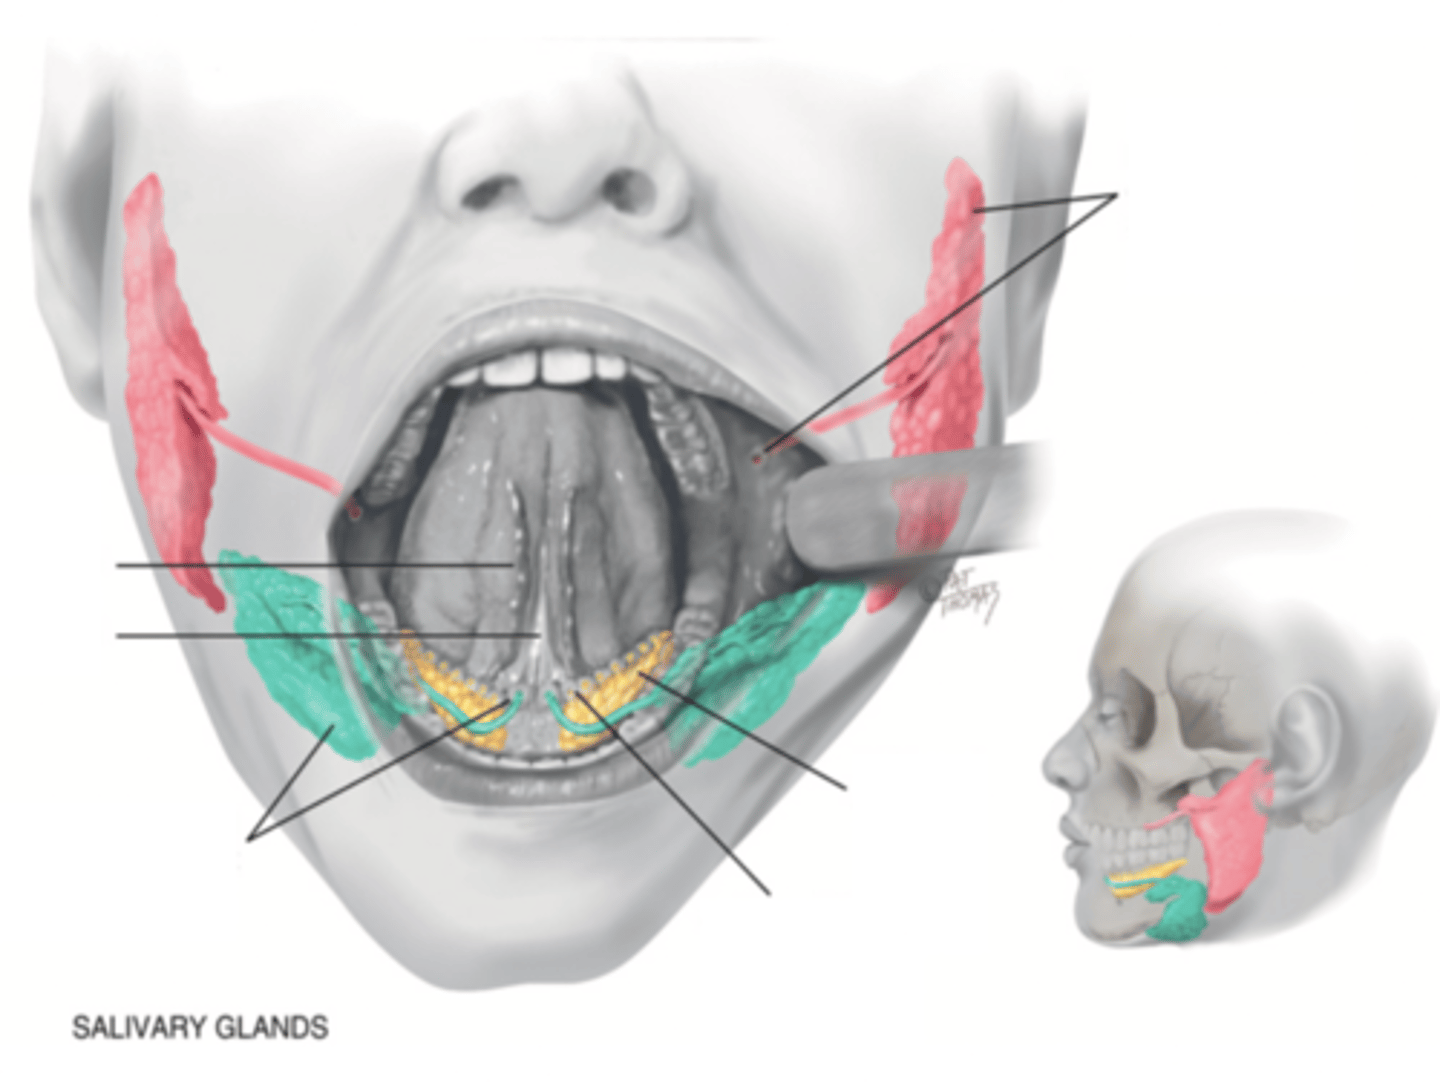

Salivary Glands

- Parotid

- Submandibular

- Sublingual

Parotid Gland

Salivary gland within the cheek, just anterior to the ear (red)

Submadibular Gland

Salivary gland under the mandible (green)

Sublingual Gland

Salivary gland under the tongue (yellow)